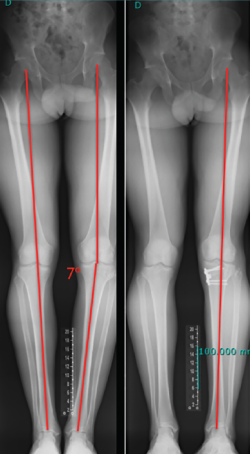

El estudio radiológico recomendado debería incluir proyecciones anteroposteriores y laterales, axiales de rótula, telemétricas de la extremidad inferior y también en posición de Schuss (en carga y con unos 30° de flexión de la rodilla). La radiología simple va a permitir identificar qué técnica quirúrgica se realizó inicialmente y qué material se utilizó para la fijación (Figura 1). La proyección en Schuss permite observar si existen cambios degenerativos en los compartimentos femorotibial interno o externo de la rodilla de forma más precisa que con la radiología simple en decúbito supino. Finalmente, la radiografía telemétrica de las extremidades inferiores va a permitir conocer el eje mecánico de la extremidad. La existencia de deformidades en el plano coronal se ha asociado a un incremento de la solicitación mecánica del LCA y también del riesgo de rotura de la plastia (Figura 2)(21).

Figura 2. Paciente de 21 años con antecedente de reconstrucción anatómica del ligamento cruzado anterior (LCA) y ángulo posteroexterno que requirió cirugía correctiva de un genu varo de 7° después de fracasar la reconstrucción ligamentosa.

Independientemente de las deformidades en el plano axial, las deformidades en el plano coronal, sobre todo el genu varo, se han relacionado también con un incremento de las solicitaciones mecánicas sobre el LCA y secundariamente como factor de riesgo de rotura(45,46).